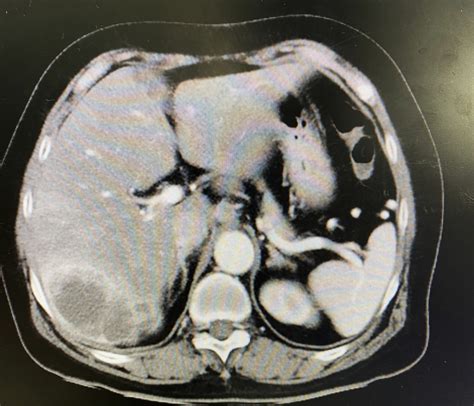

If you notice any combination of the symptoms mentioned above, it is vital to schedule an appointment with your primary care provider. They will likely start with blood tests, such as liver function tests, and may follow up with imaging studies like ultrasounds, CT scans, or MRIs to look for obstructions. Early diagnostic imaging is the most effective way to identify tumors within the biliary tract.

• Imaging: MRI/MRCP or CT scans provide detailed internal views of the bile duct anatomy.